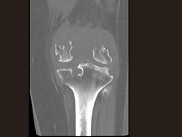

- 单项选择题男,36岁, 膝关节疼痛8年余,活动受限, 其周围可触及肿块,结合图像, 最可能的诊断是 ( )

A、骨巨细胞瘤

B、滑膜肉瘤

C、血友病性关节炎

D、色素沉着绒毛结节性滑膜炎

E、类风湿关节炎